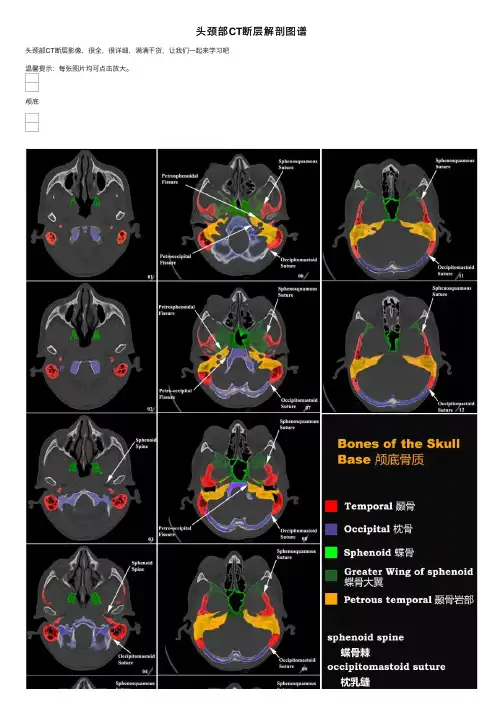

头颅1.额⾻2.额上回3.冠状缝4.中央前沟5.⼤脑镰6.中央前回7.顶⾻8.旁中央⼩叶9.中央沟 10.中央后回11.顶上⼩叶 12.楔前叶13.⽮状缝 14.上⽮状窦1.额⾻2.上⽮状窦3.额上叶4.冠状缝5.⼤脑镰6.额中回7.⼤脑纵裂8.中央前沟9.中央前回 10.中央沟 11.⼤脑⽩质(半卵圆中⼼)12.中央后回 13.旁中央⼩叶 14.缘上回 15.顶⾻ 16.顶下⼩叶 17.楔前叶 18.顶枕沟 19.枕⾻1.额⾻2.额上回3.⼤脑镰4.额中回5.扣带回6.冠状缝7.胼胝体周围动脉8.中央前回9.放射冠 10.中央沟11.胼胝体 12.中央后回13.侧脑室(脉络膜丛) 14.中央后沟 15.顶⾻ 16.缘上回 17. 楔前叶 18.⾓回 19.顶枕沟 20.枕回 21.楔叶 22.枕⾻ 23.上⽮状窦1.额⾻2.⼤脑镰3.额上回4.额中回5.额下回6.扣带回7.胼胝体⼲8.侧脑室前⾓9.尾状核头10.中央前回 11.中央沟 12.放射冠 13.中央后回 14.屏状核 15.丘脑 16.外侧裂 17.颞叶岛盖 18.脑岛 19.尾状核尾 20.颞上回 21.胼胝体压部 22.穹窿 23.扣带回峡 24. 侧脑室脉络丛 25.直窦 26.⼤脑⼤静脉27.顶⾻ 28.顶枕沟29.枕回 30.楔叶 31.上⽮状窦 32.纹状⽪层(视觉初级⽪层)33.枕⾻1.额⾻2.额窦3.额上回4.额中回5.⼤脑镰6.尾状核头7.扣带回8.额下回9.胼胝体膝部 10.内囊前肢 11.侧脑室前⾓ 12.第三脑室 13.中央沟 14.中央前回 15.穹窿 16.中央后回 17.室间孔 18.外侧裂 19.屏状核20.外侧裂池岛动脉? 21.内囊后肢 22.岛叶 23.丘脑 24.苍⽩球 25.松果体 26.壳(核) 27.尾状核尾 28.颞横回 29.⼤脑内静脉 30.海马 31.⼩脑蚓部 32.侧脑室后⾓(脉络膜丛)33.直窦 34.颞中回 35.顶⾻ 36.顶枕沟 37.上⽮状窦 38.枕回 39.枕⾻ 40.纹状⽪层(视觉初级⽪层)41.枕极1.额⾻2.额窦3.⼤脑镰4.额上回5.扣带回6.额中回7.胼胝体膝部8.侧脑室前⾓9.内囊前肢 10.尾状核头11.顶⾻ 12.额下回 13.外囊 14.壳(核)15. 前联合?16.外侧裂池岛动脉? 17.下丘脑 18.内囊膝 19.第三脑室 20.屏状核 21.颞上回 22.外囊 23.颞⾻ 24.内囊后肢 25.膝状体(内、外)26.内囊后肢 27.海马28.丘脑 29.海马旁回 30.松果体 31.⼩脑幕 32.四叠体板 33.⼩脑蚓部 34.四叠体池 35.直窦 36.颞中回 37.上⽮状窦 38.侧脑室后⾓ 39.枕⾻ 40.顶⾻ 41.枕回1.额⾻2.额窦3.⼤脑镰4.额上回5.扣带回6.额中回7.额下回8.⼤脑前动脉9.纹状体(下部)10.外侧裂(岛池)11.岛叶 12.岛动脉 13.视束 14.颞上回 15.下丘脑 16.第三脑室 17.⼤脑脚 18.顶⾻ 19.侧脑室(颞⾓) 20.脚间池 21.颞中回 22.海马 23.海马旁回 24.环池?25.中脑(四叠体板) 26.中脑导⽔管 27.颞下回 28.四叠体池 29.枕颞外侧回 30.⼩脑蚓部 31.顶枕沟 32.⼩脑幕 33.上⽮状窦 34.直窦 35.枕⾻ 36.枕回1.额窦2.额⾻3.⼤脑镰4.眶回5.直回6.⼤脑前动脉7.前交通动脉8.颈内动脉9.颞上回 10.颞中回 11.⼤脑中动脉 12.后交通动脉 13.视交叉 14.杏仁核 15.垂体 16.侧脑室(颞⾓)17.鞍背 18.海马 19.基底池?20.颞下回 21.⼤脑后动脉22.海马旁回 23.⼩脑幕 24.基底动脉和基地沟 25.桥脑 26.⼄状窦 27.⼩脑⾓(中部)28.第四脑室 29.齿状核 30.⼩脑蚓(上部)31.颞⾻ 32.窦汇 33.⼩脑半球 34.横窦 35.枕⾻1.额⾻2.额窦3.直回4.颞肌5.眶回6.眶顶7.颞上回8.视神经9.颈内动脉 10.垂体 11.颞中回 12.鞍背13.海马旁回 14.基底动脉 15.侧脑室(颞⾓) 16.颞下回17.三叉神经 18.滑车神经 19.脑桥池 20.乳突窦21.⼩脑幕 22.第四脑室 23.桥脑 24.颞⾻ 25.⼩脑脚 26.⼩脑蚓 27.⼄状窦 28.⼩脑半球 29.齿状核 30.枕窦 31.枕⾻ 32头半棘肌1.额⾻2.额窦3.上斜肌4.眼球5.眼静脉6.上直肌7.直回合嗅球8.眶后脂肪9.颞肌 10.视神经 11.蝶窦 12.蝶⾻ 13.颞下回 14.眶上组织 15.三叉神经 16.颈内动脉 17.桥脑池 18.海绵窦 19.乳突窦 20.基底动脉 21.桥脑 22.脑桥⼩脑池 23.⼩脑脚中下部 24.⾯、前庭蜗神经(内⽿道)25.⼄状窦 26.乳突和乳突细胞27.⼩脑蚓 28.第四脑室 29.枕窦 30.⼩脑半球 31.枕⾻32.头半棘肌1.眼球2.上斜肌3.泪腺4.筛⾻窦5.颧⾻6.内直肌7.视神经8.外直肌9.蝶⾻ 10.上直肌 11.颞肌 12.蝶窦13.颞⾻ 14.颞叶(底部)15.斜坡(由颅⾻的枕⼤孔向上⾄背鞍)16.颞下颌关节和下颌头17.基底动脉18.颈内动脉19.外⽿道(⾻膜)20.⿎室 21.桥脑 22. 外展神经 23.绒球 24.⼩脑下前动脉 25.乳突和乳突细胞 26.⾆咽神经和迷⾛神经 27.⼄状窦 28.延髓 29.头夹肌 30.⼩脑半球 31.枕⾻ 32.枕窦 33.头后⼩直肌 34.头半棘肌1.⿐⾻2.眼球3.内直肌4.⿐中隔5.筛⾻窦6.颧⾻7.翼腭窝8.下直肌9.枕⾻(基底部) 10.颞肌 11.卵圆孔下颌神经 12.蝶窦 13.颞⾻(岩顶部)14.颧⼸ 15.颈内动脉 16.咀嚼肌 17.颈静脉 18 翼外机 19.外⽿道 20.咽⿎管 21.延髓 22.下颌头 23.乳突 24.破裂孔 25.⼄状窦 26.椎动脉 27岩枕裂.28.绒球 29.⼩脑扁桃体30.⼆腹肌 31.头夹肌 32.⼩脑半球(尾叶)33.头后⼩直肌 34.⼩脑延髓池 35.头后⼤直肌 36.枕⾻ 37.头半棘肌 38.斜⽅肌来源:⿍湖影像。